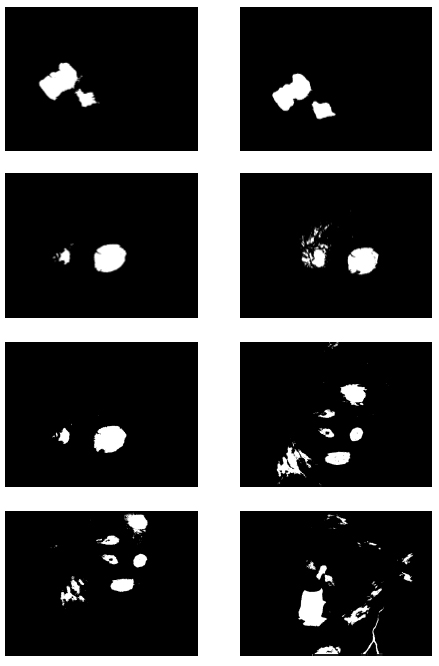

In the first part of the experiments, the effects of the score and penalty values for two iteration values were studied. All runs have been done for two neighborhood sizes of 3×3 and 5×5. Samples of the original retinal images with hard exudates are shown in (Figs. 1-3) show noisy images and the images denoised by the ripplet transform-based denoising method presented in this paper. Segmented images of retinal images are shown in Fig. (4). The images in Fig. (4) correspond to the implementation of the proposed method with a marginally optimum set of parameters, while their numerical results are given in Table 2. The results of statistical analysis on the score and penalty assignments are given in Table 2 while the proposed method is used with and without the denoising process. It is shown that the optimum score and penalty values stand about 0.01 and 0.02 while the product of score/penalty values and the number of iterations is important. The denoising process improves the statistical parameters of about 4-6%. It is also shown that for our dataset images, the neighborhood size of 5×5 which is an extended Moore neighborhood, leads to better results as compared to the simple Moore neighborhood.

![]() |

Fig. (4).

Segmented Retinal Images by the FCLA after the denoising process while

.

|